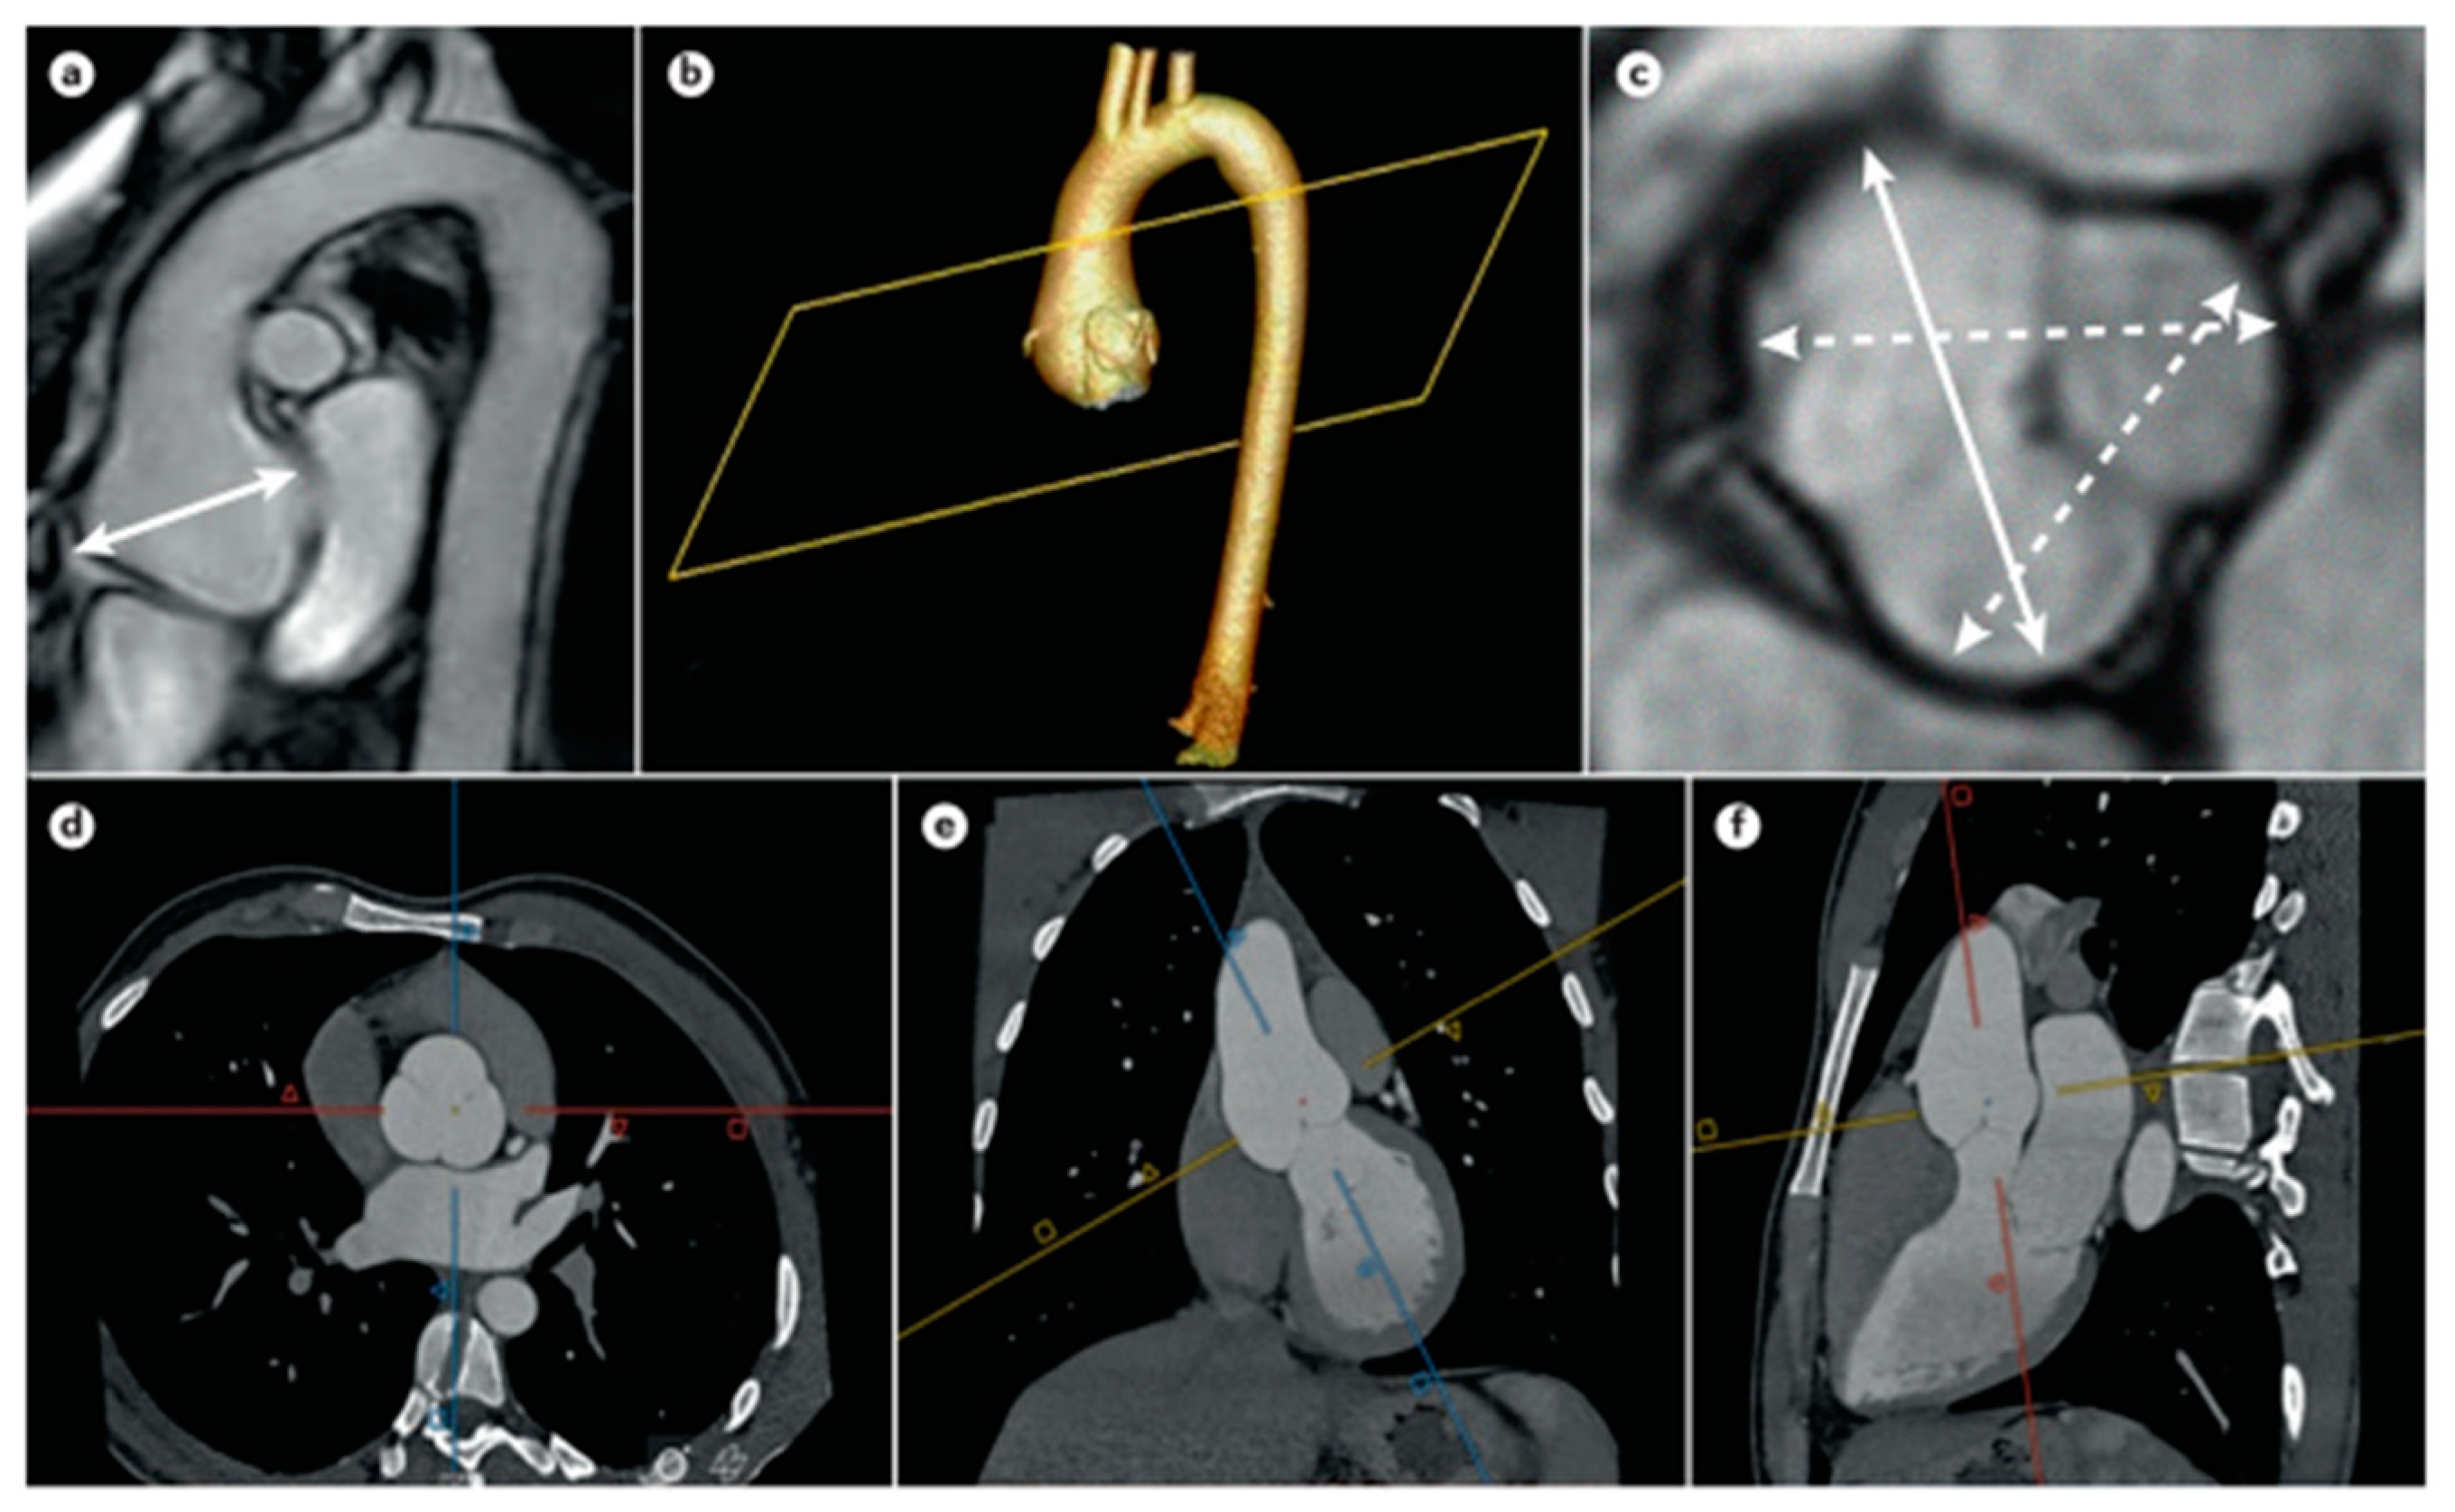

- Tijmes, F.S.; Karur, G.R. Imaging of Heritable Thoracic Aortic Disease. Semin. Roentgenol. 2022, 57, 364–379. [Google Scholar] [CrossRef]

- Zhuang, B.; Sirajuddin, A.; Zhao, S.; Lu, M. The role of 4D flow MRI for clinical applications in cardiovascular disease: Current status and future perspectives. Quant. Imaging Med. Surg. 2021, 11, 4193–4210. [Google Scholar] [CrossRef]

- Russo, V.; Renzulli, M.; La Palombara, C.; Fattori, R. Congenital diseases of the thoracic aorta. Role of MRI and MRA. Eur. Radiol. 2006, 6, 676–684. [Google Scholar] [CrossRef]